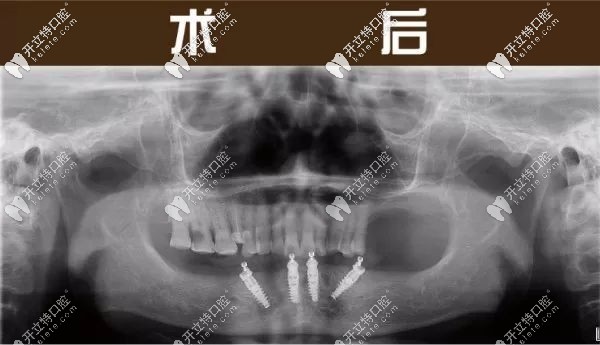

(下半口做完4顆種植牙的全景片圖) ↑